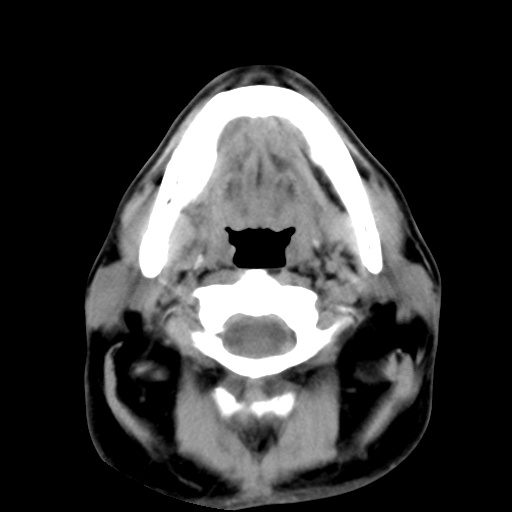

标题: CT24019:男,45岁,发现颈部肿物5个月。 [打印本页]

男,45岁,发现颈部肿物5个月,彩超示:双侧颈部及下颌部软组织增厚。

考虑双侧颈项部良性对称性脂肪增多症。